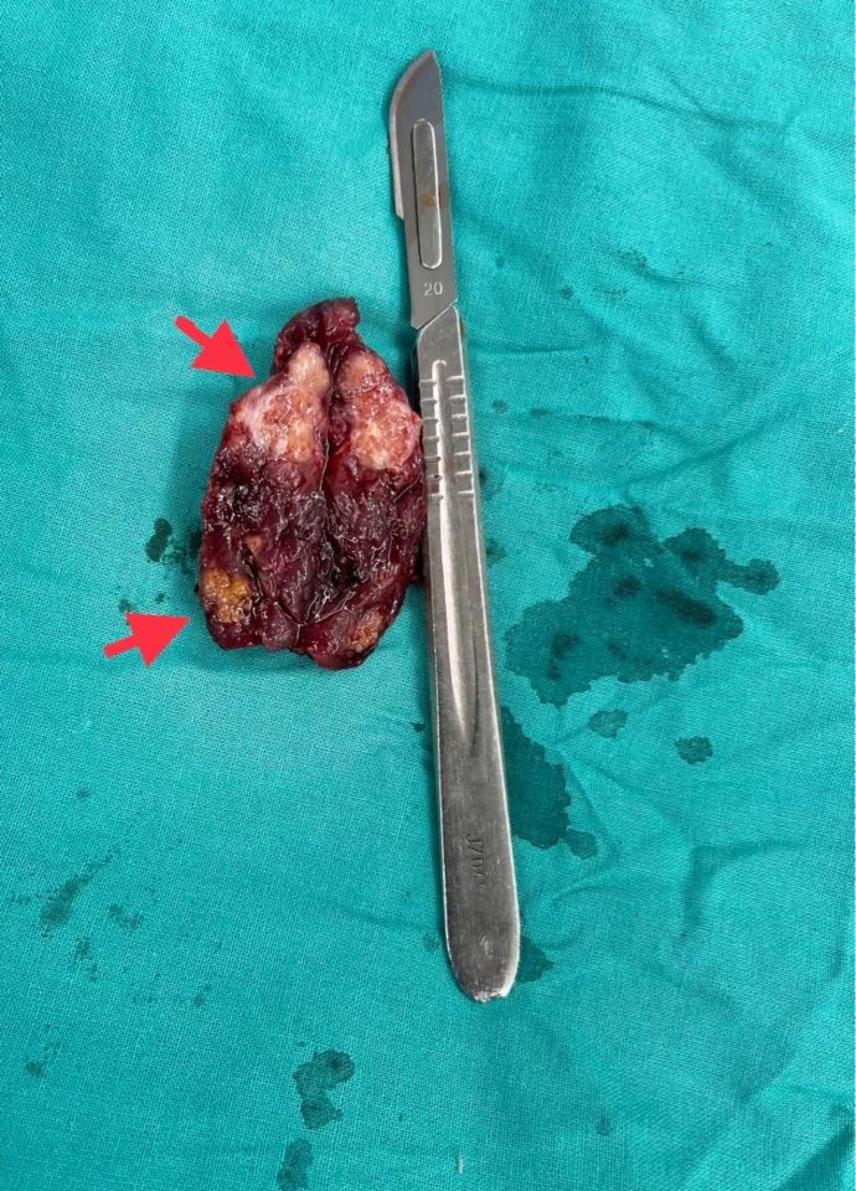

甲状腺良性肿瘤恶变甲状腺未分化癌1例原创